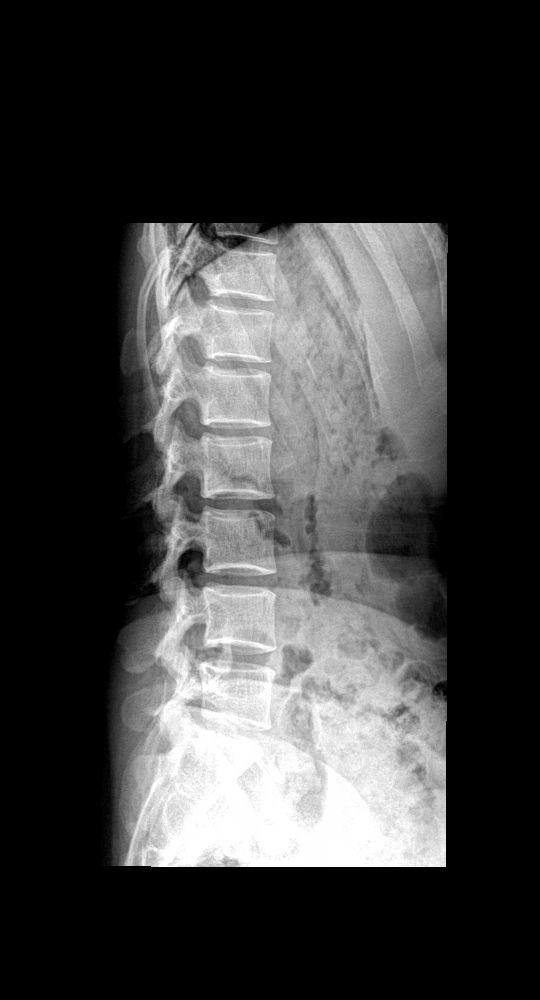

女 35岁 下肢麻木